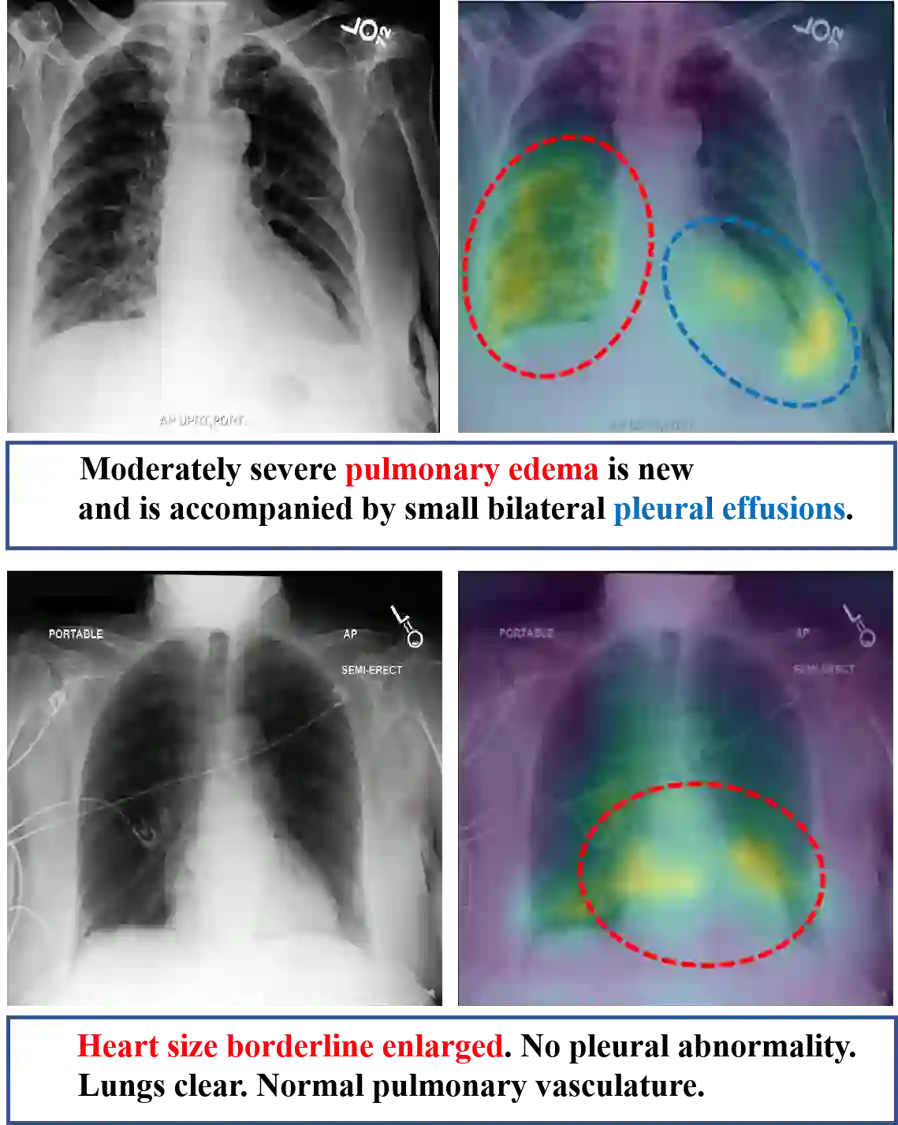

Recently a number of studies demonstrated impressive performance on diverse vision-language multi-modal tasks such as image captioning and visual question answering by extending the BERT architecture with multi-modal pre-training objectives. In this work we explore a broad set of multi-modal representation learning tasks in the medical domain, specifically using radiology images and the unstructured report. We propose Medical Vision Language Learner (MedViLL) which adopts a Transformer-based architecture combined with a novel multimodal attention masking scheme to maximize generalization performance for both vision-language understanding tasks (image-report retrieval, disease classification, medical visual question answering) and vision-language generation task (report generation). By rigorously evaluating the proposed model on four downstream tasks with two chest X-ray image datasets (MIMIC-CXR and Open-I), we empirically demonstrate the superior downstream task performance of MedViLL against various baselines including task-specific architectures.